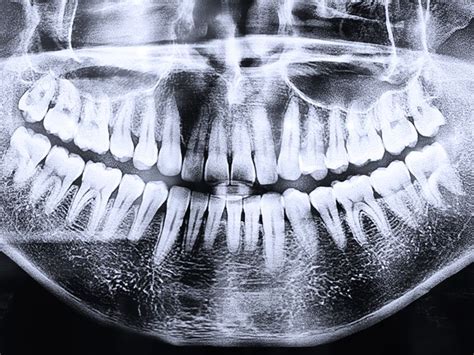

El método de diagnóstico utilizado para detectar la presencia de retención dentaria es la pantomografía, una radiografía panorámica en la que en una sola imagen pueden verse los maxilares superior e inferior y la disposición de los dientes.

Radiografía panorámica dental (Pantomografía).